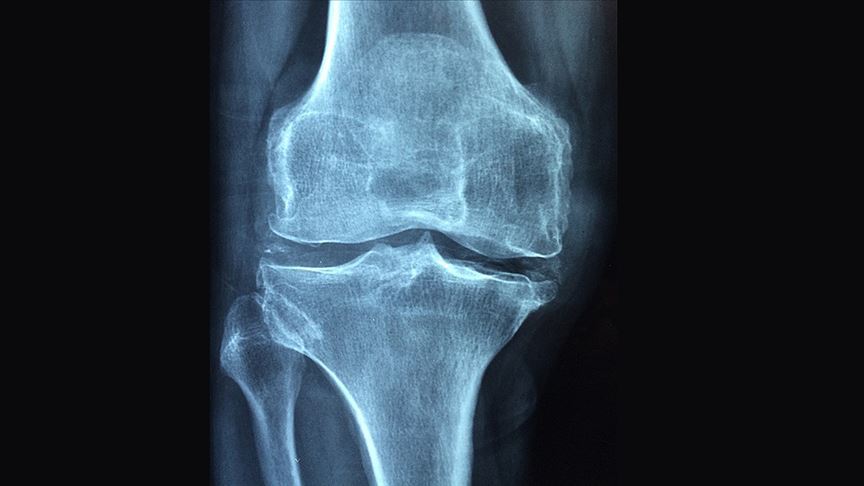

Romatizmal hastalıkların aynı zamanda osteoporoz gelişimi için de bir risk faktörü olduğunu vurgulayan Günendi, "Yapılan çalışmalarda iltihabi romatizmal hastalığı olanlarda, aynı yaş ve cinsiyetteki sağlıklı kişilere göre osteoporoz görülme sıklığının arttığı gösterilmiştir." dedi.

Osteoporoz ve osteoporoza bağlı kırıkların, romatizmal hastalığın kişiye ve topluma getirdiği yükün daha da artmasına neden olduğunu dile getiren Günendi, "Bu nedenlerle romatizmal hastalıklı kişilerde osteoporoz gelişiminin daha sık olabileceği unutulmamalı, diyet ve egzersiz gibi önleme girişimleri, uygun tarama yöntemleriyle erken tanı ve gerekiyorsa tedavi girişimleri yürütülmeli." ifadelerini kullandı.

"Romatizmal hastalıklarda osteoporoz gelişiminde en önemli neden, altta yatan iltihaptır." bilgisini veren Prof. Dr. Günendi, iltihabın gelişimi aşamasında bağışıklık sisteminin de bozulduğunu söyledi.

Bağışıklık sisteminde, hücreler arası etkileşimi sağlayan sitokin adı verilen protein yapıların olduğunu anlatan Günendi, "Bunların bazıları iltihabı tetiklerken bazıları da iltihap gelişimini önlemektedir. Sağlıklı kişilerde sitokinler denge içinde bulunurken, romatizmal hastalığı olan bireylerde sitokin dengesi, iltihabı tetikleyen sitokinlere doğru kaymaktadır. Romatizmal hastalıklarda artmış iltihap tetikleyici sitokinler, aynı zamanda kemik yıkımını da hızlandırmaktadır." diye konuştu.